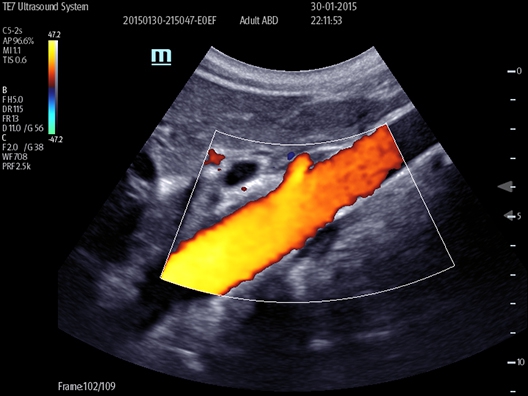

УЗИ-аппарат

Mindray TE7

Ультразвуковой аппарат Mindray TE7 представляет собой компактное решение, идеально подходящее для проведения оперативных диагностических исследований за пределами больницы. В отличие от других моделей бренда, основным отличием этого устройства является отказ от стандартной клавиатуры, вместо которой используется только сенсорный экран. Такой подход получил положительные отзывы на рынке, поскольку он позволяет избежать необходимости нажимать множество кнопок и переключать между различными опциями.

Mindray TE7 является удачным выбором, поскольку он обеспечивает новый уровень современной ультразвуковой диагностики. Важным преимуществом является встроенный аккумулятор, который позволяет аппарату работать автономно за пределами больницы.

• Функция интеллектуальной оптимизации изображения при сканировании сосудов Smart Track: непрерывное цветовое обозначение; оптимизация положения и угла цветового поля при сканировании в режиме реального времени.